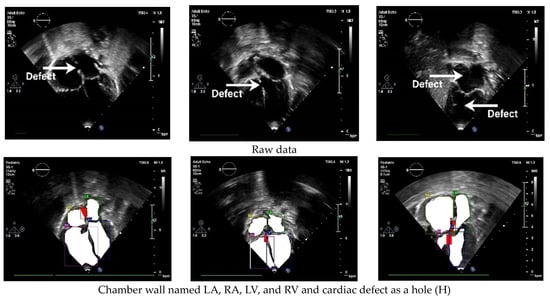

The standard cardiac view of US video recordings has consisted of A4CH, A5CH, PLAX, PSAX, and SC. Pediatric cardiologists rely on specific views when assessing a patient’s condition. The annotation of the three CSD conditions is presented in Figure 3 using LabelMe 5.3.1 software. The annotated sample results in showcasing the chamber wall area and the cardiac defect area. Atrial or ventricular areas are represented by the white regions, while the red region denotes a cardiac defect area.

Figure 3. Annotation of chamber wall and cardiac defect.